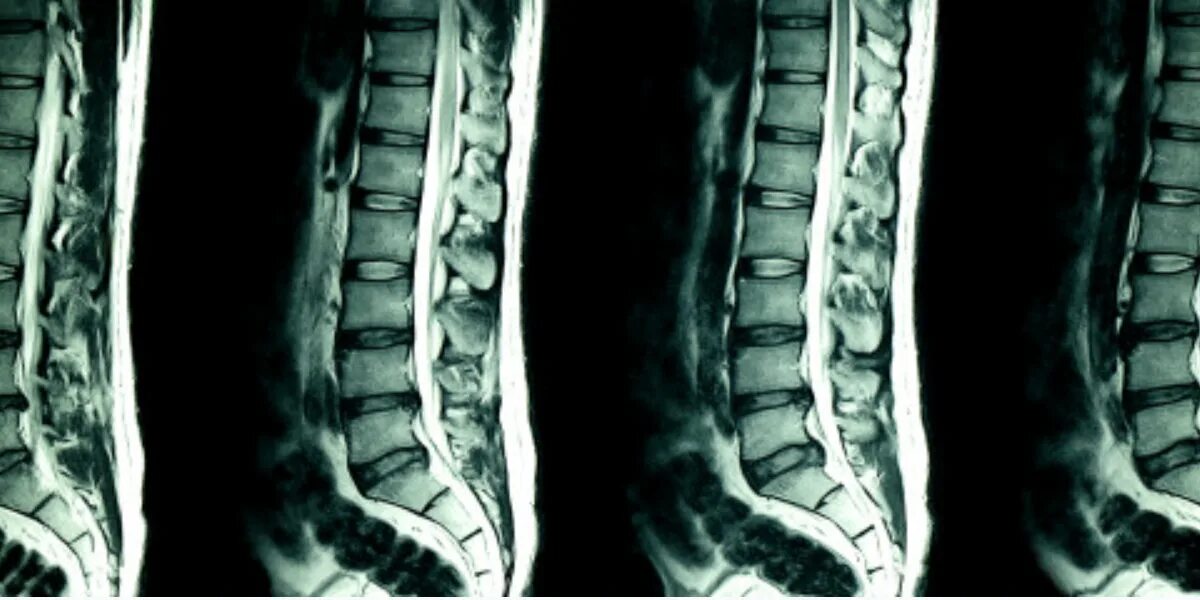

Мрт или кт позвоночника при болях